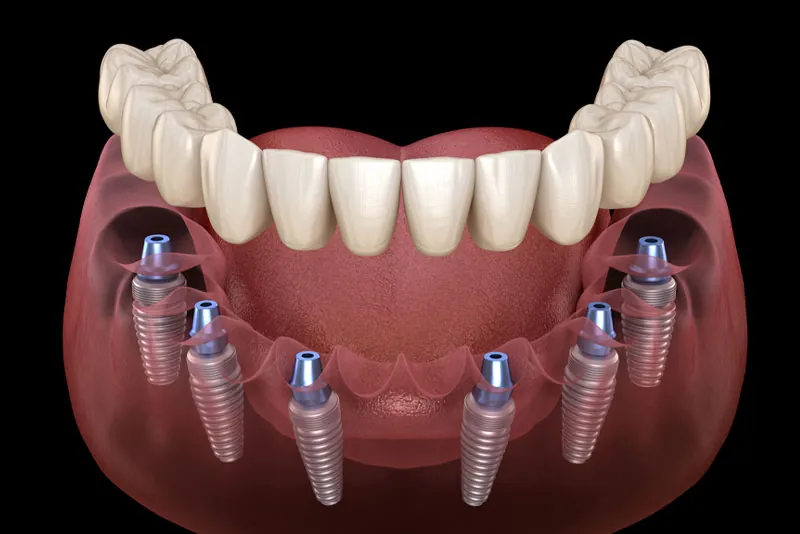

Full Mouth Implants

A complete smile transformation with secure, fixed implants replacing the entire arch.